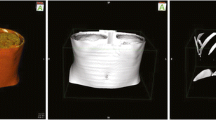

Stone of Orthanc takes the form of a lightweight, cross-platform C++ toolkit. As Stone of Orthanc is entirely written in pure C++ and is entirely standalone, it can easily be embedded into heavyweight software (C++ support comes out of the box, and bindings to Java and C# are in active development) or into native mobile applications (Android and iOS). Very importantly, the Stone of Orthanc is compatible with the emerging WebAssembly technology that can be used to run C++ applications in Web browsers without installing any browser extension [22]. As a consequence, thanks to the Stone of Orthanc, it is possible to benefit from a single codebase to quickly write applications for displaying and/or analyzing medical images, and targeting any kind of platform (native, mobile or Web). Figure 14 shows some rendering produced by the Stone of Orthanc toolkit.